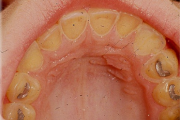

Suulaepoolt lõikunud koonilise kujuga lisahammas